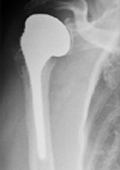

Wenn der Verschleiß im Bereich der Schulter bereits erheblich ausgeprägt ist und alltägliche Bewegungen und Handlungen starke Schmerzen verursachen, hat man die Möglichkeit, durch die Implantation eines künstlichen Gelenks den Betroffenen zu helfen und ein großes Stück an Lebensqualität zurückzugeben.

Wie auch bei den anderen großen Gelenken hat man bei der Schulter die Möglichkeit eines endoprothetischen Ersatzes. Hier hat man die Wahl zwischen verschiedenen Prothesenarten, wobei die Prothesenwahl abhängig vom Ausmaß des vorliegenden Gelenkverschleißes und des Zustandes der stabilisierenden Weichteile (Rotatorenmanschette) ist.

Liegt nur ein isolierter oder ganz lokalisierter Verschleiß des Oberarmkopfes vor, kann ein Ersatz des Oberarmkopfes allein ausreichend sein. Hier haben die Operateure im Zentrum für Orthopädie und Unfallchirurgie mehrere solcher Teilprothesen zur Auswahl.

Sind die degenerativen Veränderungen auch im Bereich der Pfanne voran geschritten, wird diese in den meisten Fällen ebenfalls ersetzt und eine Totalprothese implantiert.

Zeigt sich bei den Betroffenen eine Ruptur der Rotatorenmanschette mit daraus resultierendem Hochstand des Oberarmkopfes, muss dies bei der Prothesenwahl berücksichtigt werden. Hier hat man die Möglichkeit, mit Hilfe der sogenannten umgekehrten bzw. der inversen Schulter-TEP die nicht mehr vorhandenen und funktionslosen Muskeln zu ersetzen, in dem man durch das umgekehrte Prothesen-Design den einzigen noch vorhandenen Muskel, den Deltamuskel, in seiner Kraftentfaltung optimiert.

Wann immer es die individuelle knöcherne Situation erlaubt werden für den Oberarm schaftfreie Verankerungen gewählt, so dass eine knochensparende Implantation möglich ist.